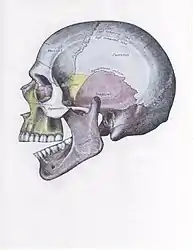

The joint involved with jaw dislocation is the temporomandibular joint (TMJ). This joint is located where the mandibular condyles and the temporal bone meet.[4][6] Membranes that surround the bones help during the hinging and gliding of jaw movement. For the mouth to close it requires the following muscles: the masseter, temporalis, and medial pterygoid muscle. For the jaw to open it requires the lateral pterygoid muscle.[4]